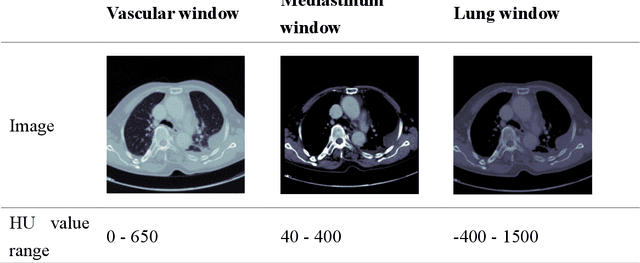

Abstract:The purpose of this research is to develop a system that generates simulated computed tomography pulmonary angiography (CTPA) images clinically for pulmonary embolism diagnoses. Nowadays, CTPA images are the gold standard computerized detection method to determine and identify the symptoms of pulmonary embolism (PE), although performing CTPA is harmful for patients and also expensive. Therefore, we aim to detect possible PE patients through CT images. The system will simulate CTPA images with deep learning models for the identification of PE patients' symptoms, providing physicians with another reference for determining PE patients. In this study, the simulated CTPA image generation system uses a generative antagonistic network to enhance the features of pulmonary vessels in the CT images to strengthen the reference value of the images and provide a basis for hospitals to judge PE patients. We used the CT images of 22 patients from National Cheng Kung University Hospital and the corresponding CTPA images as the training data for the task of simulating CTPA images and generated them using two sets of generative countermeasure networks. This study is expected to propose a new approach to the clinical diagnosis of pulmonary embolism, in which a deep learning network is used to assist in the complex screening process and to review the generated simulated CTPA images, allowing physicians to assess whether a patient needs to undergo detailed testing for CTPA, improving the speed of detection of pulmonary embolism and significantly reducing the number of undetected patients.